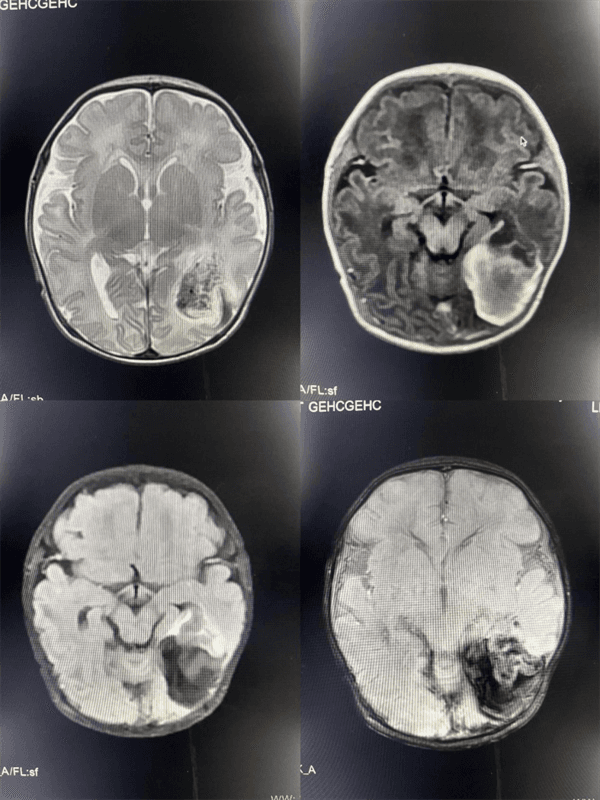

检查结果很快出来了:影像清晰地显示,宝宝左侧部分颞叶、枕叶存在亚急性脑出血,并且血肿已经破入双侧侧脑室。同时,MRA检查还发现了右侧大脑前动脉的发育异常。这份精准的影像报告,就像一张清晰的“大脑地图”,让临床医生对宝宝的病情一目了然,使得治疗更加“有的放矢”。